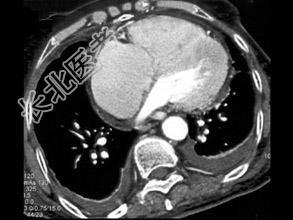

- 单项选择题男,38岁, 反复咳嗽、咳痰伴发热15年余,痰结核菌素试验(—), 结合CT图像,最可能的诊断是 ( )